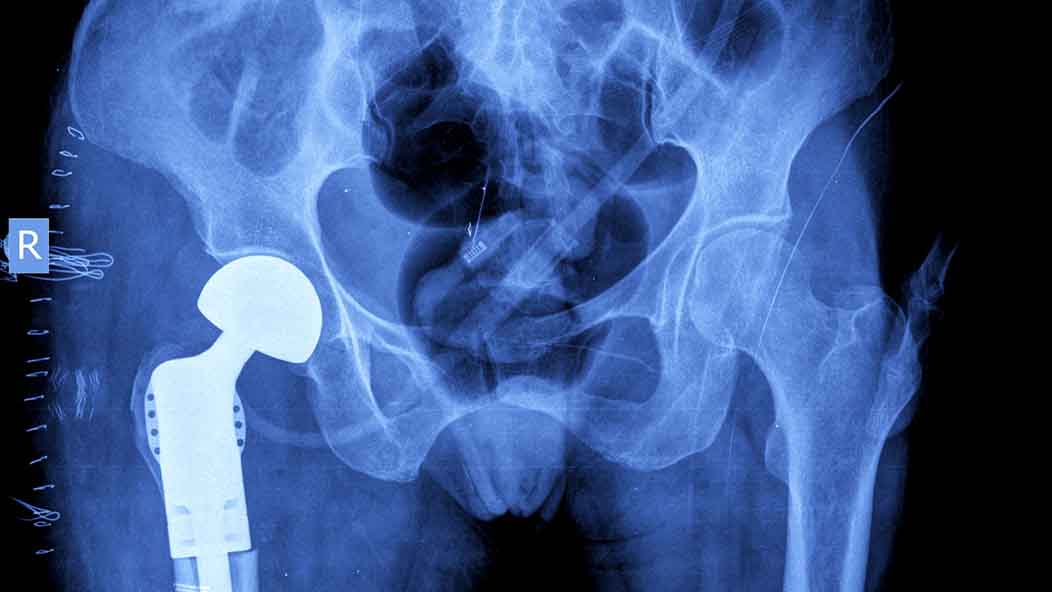

Hip replacement is a surgery in which diseased parts of the hip joint are removed and are replaced with a prosthetic implant. Hip replacement surgery is recommended by physicians when other treatments do not relieve pain. Prior to surgery, patients may choose using a cane or walker for stability, physical therapy, medication and other measures prior to hip replacement therapy.

Some people decide hip replacement surgery won’t help their pain because it’s a one-size-fits-all procedure that doesn’t cater to each patient’s needs. There are actually three different methods a surgeon may use for hip replacement: direct anterior, anterolateral, or posterolateral. All approaches are muscle sparing compared to older techniques and allow faster recovery. There are many different prosthetic implant designs that can allow for precise implant sizing for all patient sizes.

As with any surgery, there are risks with hip replacement surgery, but with technological and medical advances, complications are rare. In the past, hip dislocation, blood clots, and infection were recognized following surgery, but new surgical techniques, rapid recovery protocols, improved prosthetic design and materials have made hip replacement surgery safer and more effective than ever.